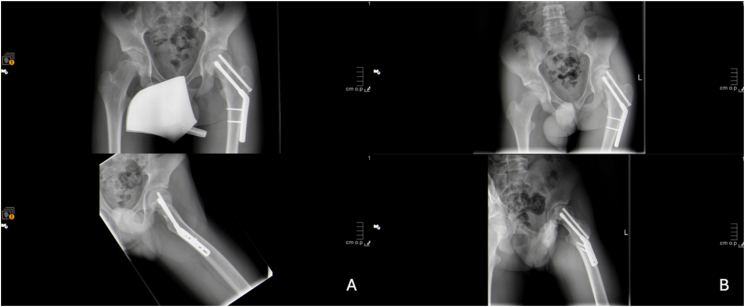

Abstract Image